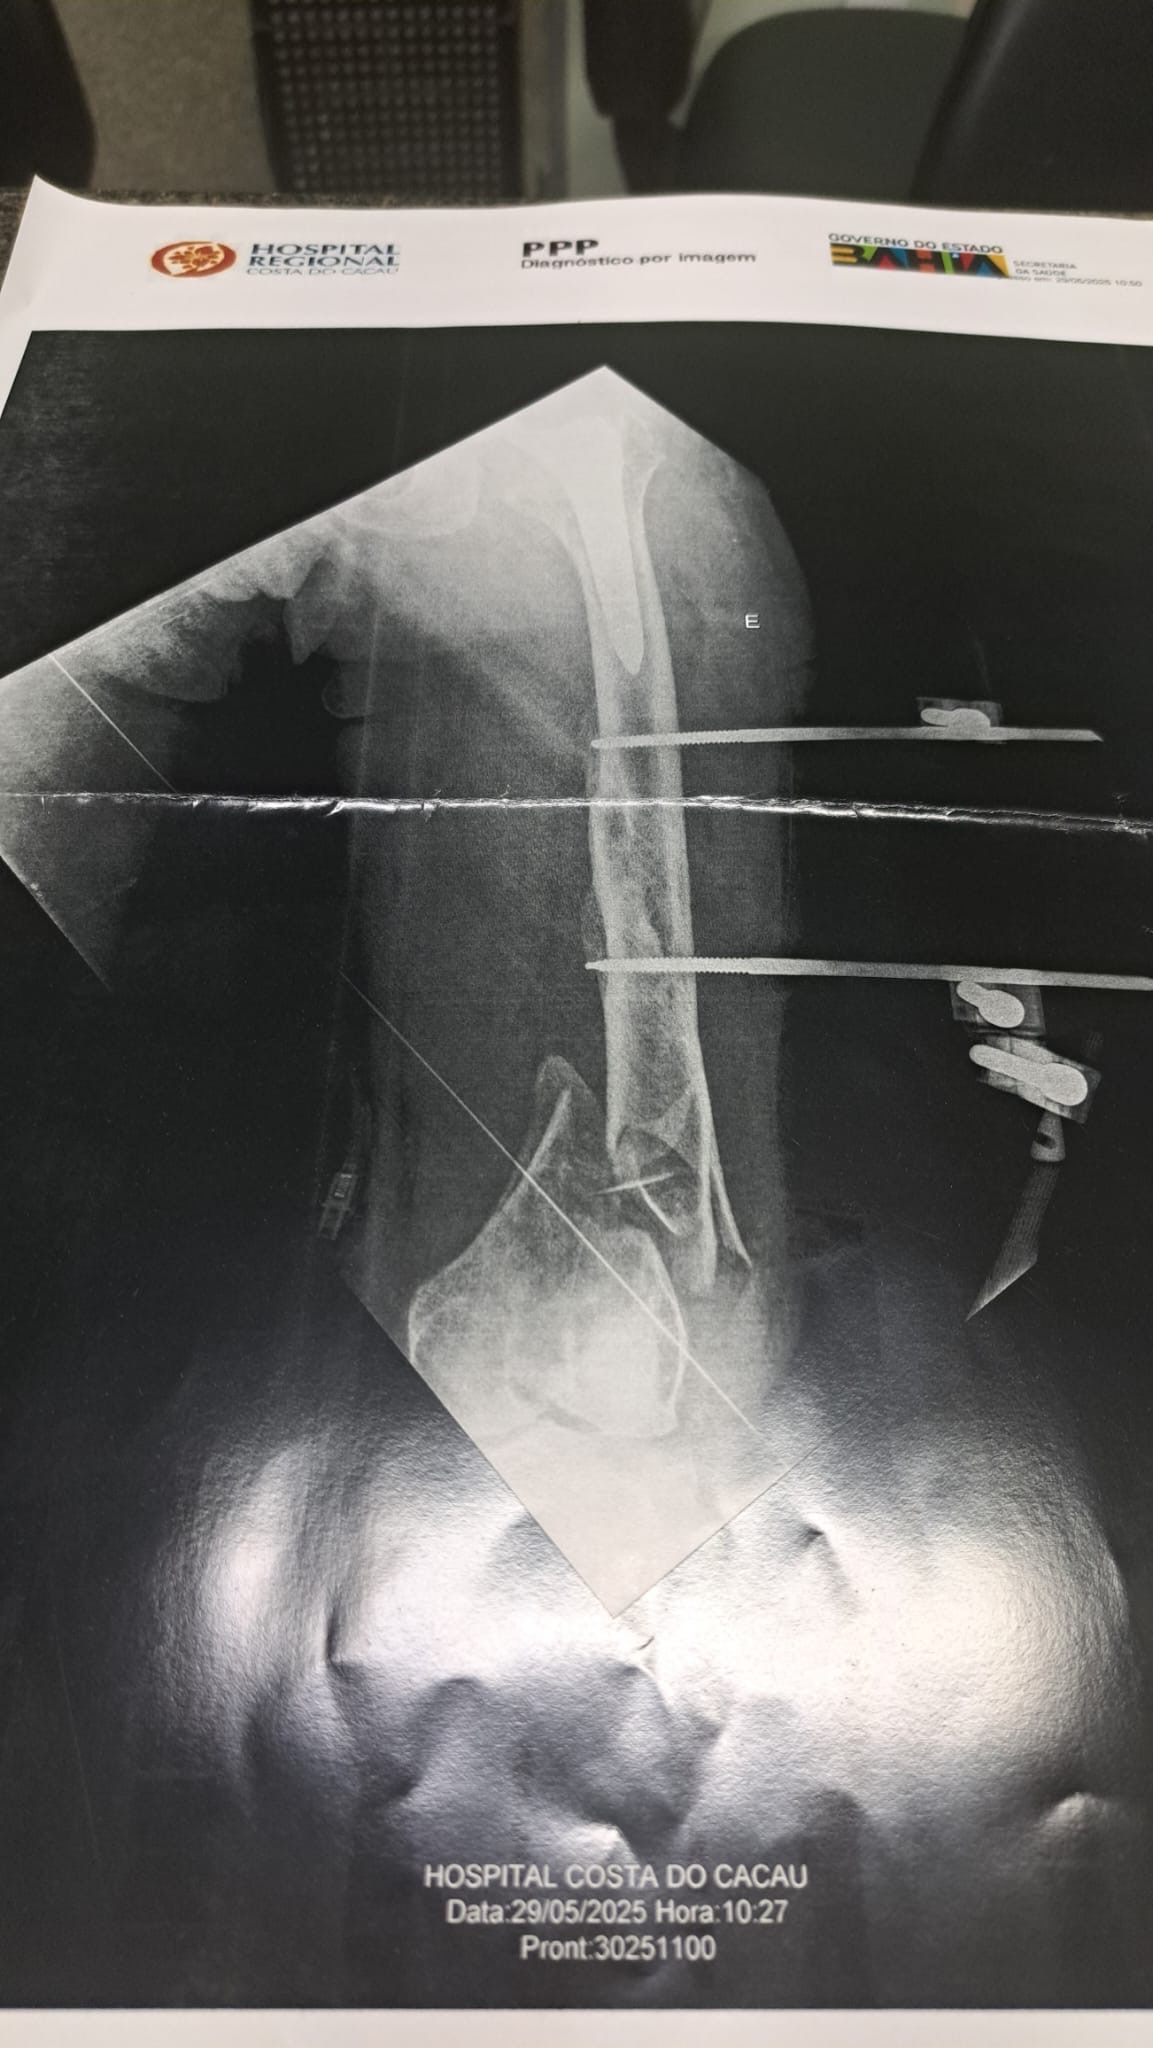

Unsere liebe Freundin Harriet wurde in Brasilien von einem Auto angefahren – ein tragischer Unfall, der ihr Leben von einem Moment auf den nächsten völlig verändert hat. Sie erlitt dabei 14 Knochenbrüche, verteilt über ihren gesamten Körper.

Seitdem liegt sie im Krankenhaus, mit unzähligen Schrauben und Metallstangen im Körper, voller Schmerzen. Die medizinischen Bedingungen vor Ort sind katastrophal, und die behandelnden Ärzte haben ihr gesagt, dass sie nichts mehr für sie tun können.